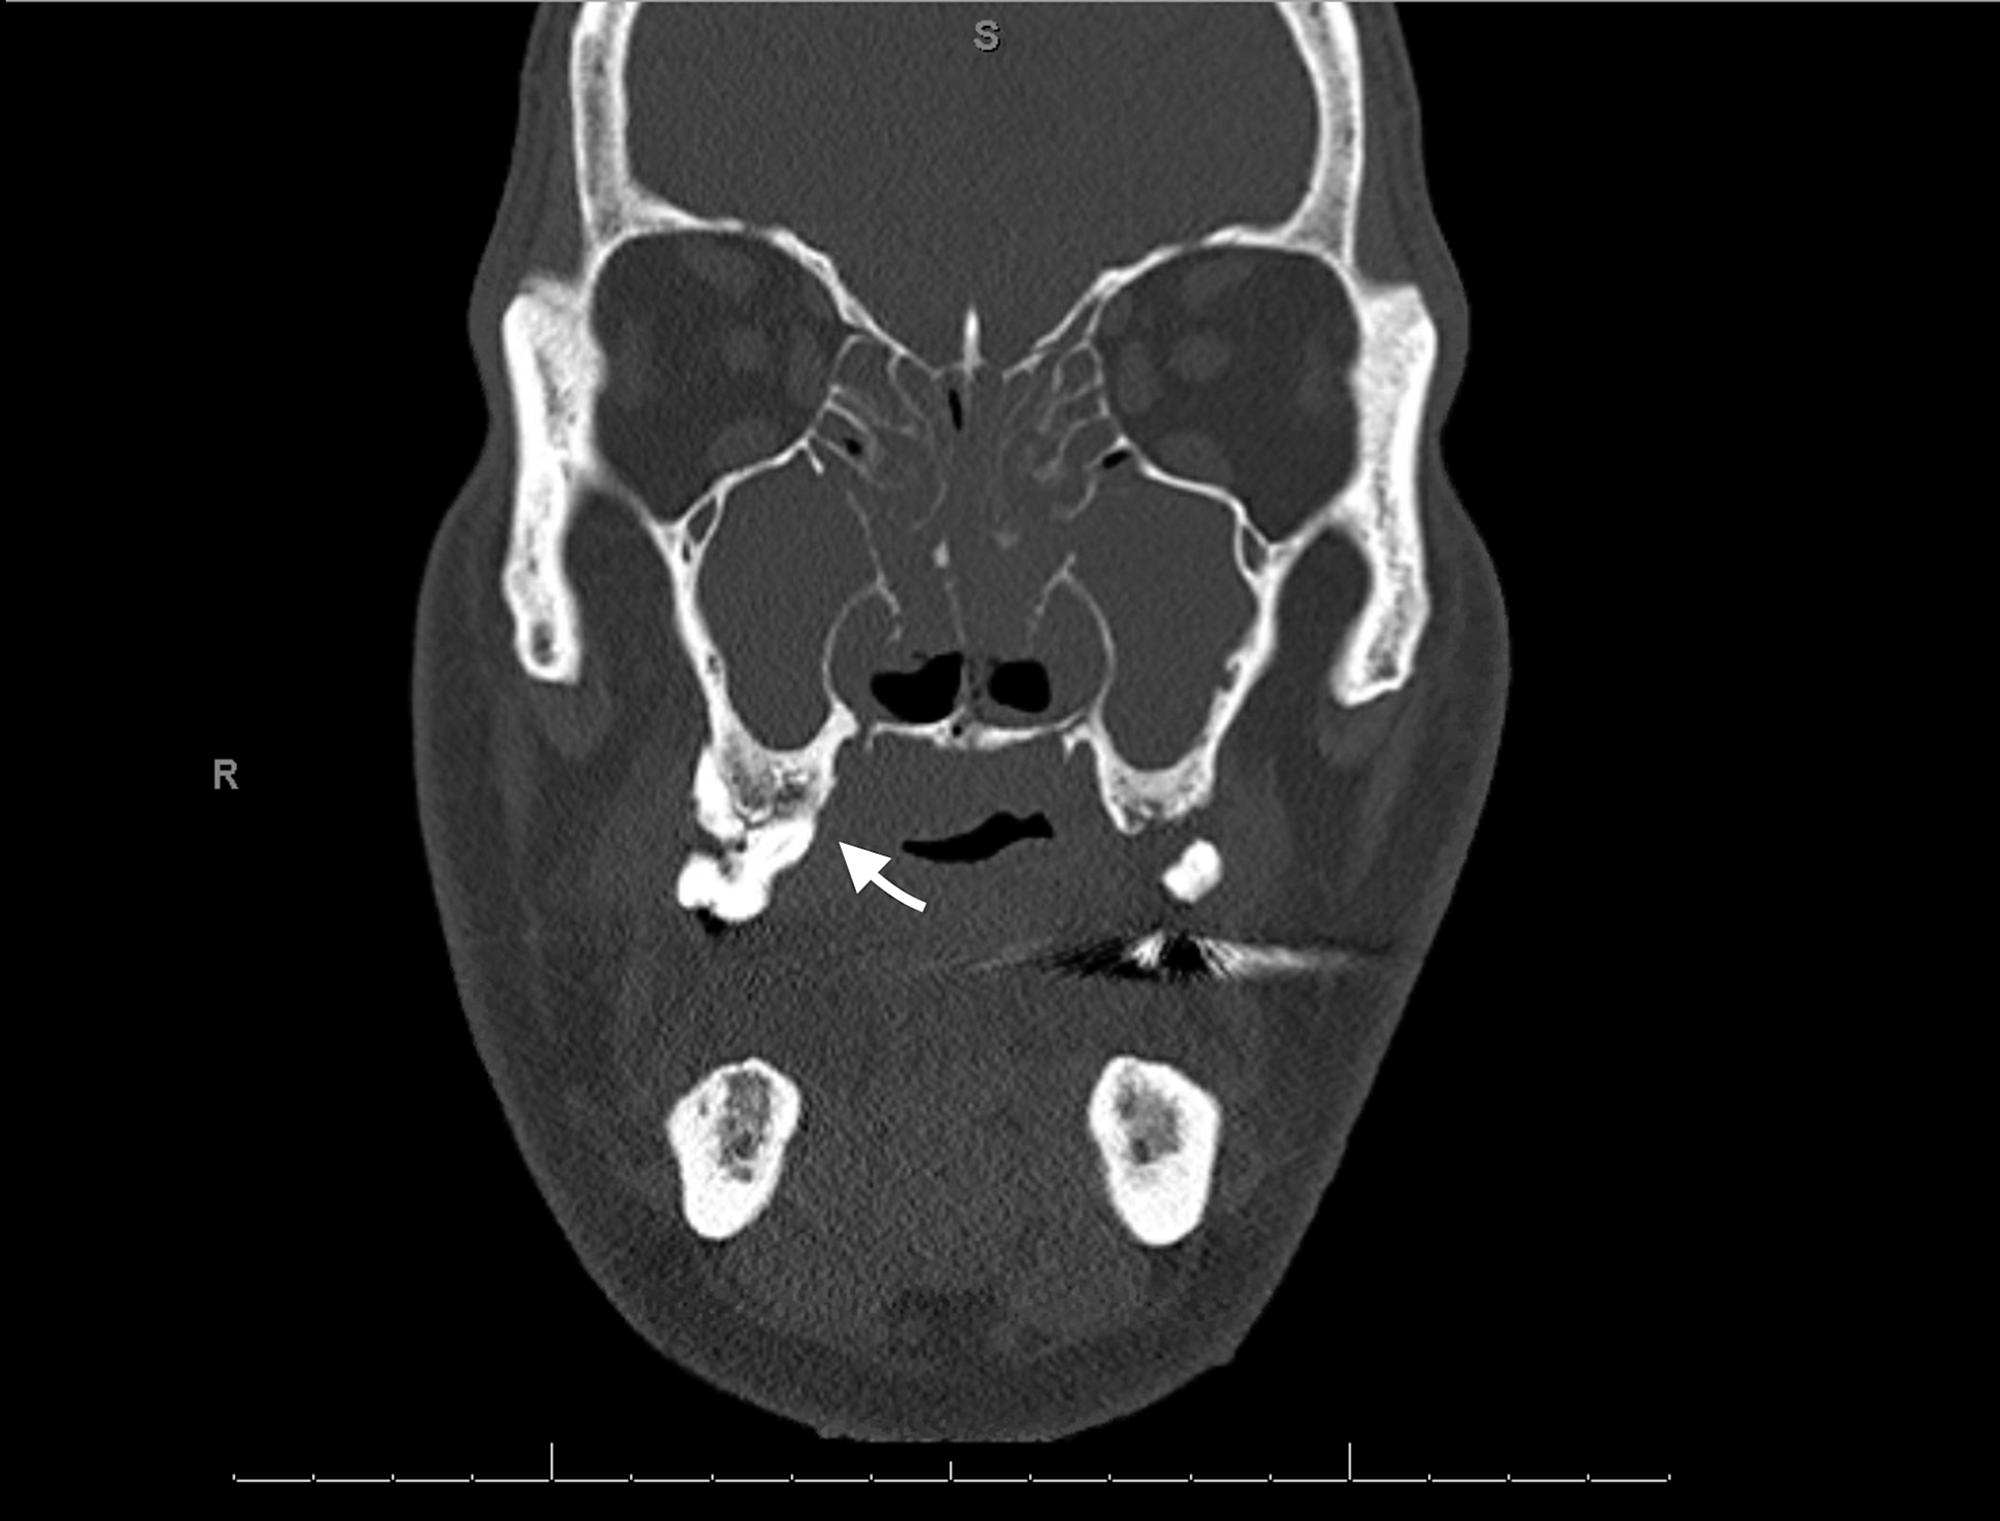

Axial CT head showing polypoidal mucosal thickening of right maxillary Maxillary Sinus Osteoma Ct to assess the maxillary sinus ostium (mso) dimension and measuring the distance to nearby anatomical structures. ct scan showing the incidental finding of a small osteoma located in the floor of the left maxillary sinus. ct scan showing an osteoma and mucosal thickening in the right maxillary antrum and polypoidal mass in the left. As in our. Maxillary Sinus Osteoma Ct.

Maxillary Sinus Osteoma Ct . As in our study, literature reports a majority of. ct scan showing an osteoma and mucosal thickening in the right maxillary antrum and polypoidal mass in the left. to assess the maxillary sinus ostium (mso) dimension and measuring the distance to nearby anatomical structures. routine cts are said to reveal approximately 1% of osteomas [1], [2]. surgical excision represents the unequivocal treatment modality for symptomatic paranasal sinus osteomas. computed tomography (ct) of the head and paranasal sinuses was performed, which revealed a solitary exophytic osseous. ct scan revealed a pedunculated bony mass arising from the lateral wall of the maxillary antrum (fig. ct scan showing the incidental finding of a small osteoma located in the floor of the left maxillary sinus.